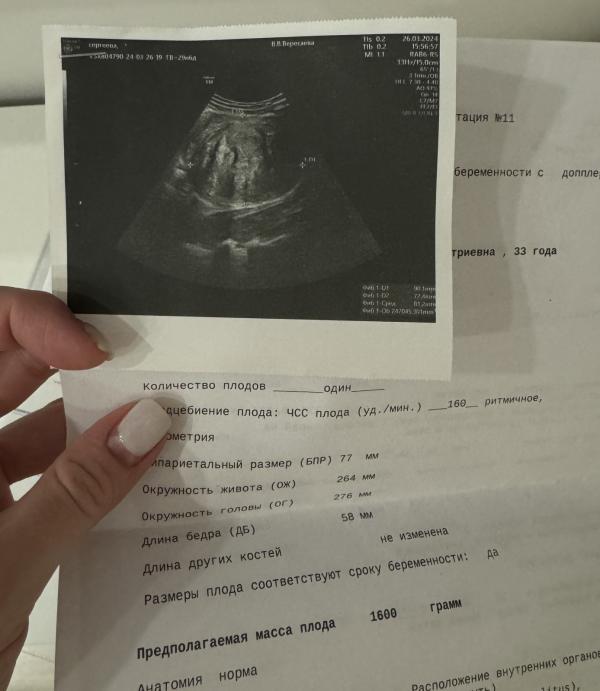

Пошла 31 неделя

Вес +9 кг

Малыш 1600 гр

Миома пока больше не растет 🙏🏻